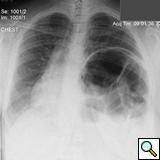

On physical exam she was obese (BMI 34) but in good general condition. There were no abnormalities on the thoracic and abdominal examination other than reduced breath sound at the left lung base. A chest x-ray showed substantial elevation of the left hemidiaphragm (Figure 1). A chest CT showed a massively distended left colon under the left diaphragm (Figure 2). A “sniff test” (fluoroscopic assessment of diaphragmatic function) showed paradoxical motion of the elevated hemidiaphragm.